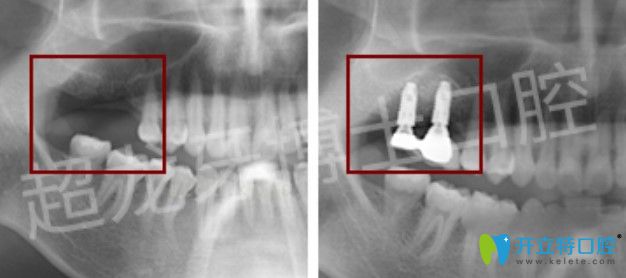

牙博士口腔成人齙牙矯正+多顆牙種植案例:

矯正案例:

牙齒情況:齙牙

矯正方式:金屬自鎖托槽矯正

種植案例:

牙齒情況:多顆牙缺失

種植技術(shù):微創(chuàng)無(wú)痛種植技術(shù)